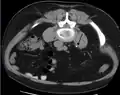

Otherwise a noncontrast helical CT scan with 5 millimeters (0.2 in) sections is the diagnostic method to use to detect kidney stones and confirm the diagnosis of kidney stone disease.[13][47][51][52][7] Near all stones are detectable on CT scans with the exception of those composed of certain drug residues in the urine,[53] such as from indinavir. Calcium-containing stones are relatively radiodense, and they can often be detected by a traditional radiograph of the abdomen that includes the kidneys, ureters, and bladder (KUB film).[53] Some 60% of all renal stones are radiopaque.[51][54] In general, calcium phosphate stones have the greatest density, followed by calcium oxalate and magnesium ammonium phosphate stones. Cystine calculi are only faintly radiodense, while uric acid stones are usually entirely radiolucent.[55]

Measurement of a 5.6 mm large kidney stone in soft tissue versus skeletal CT window.